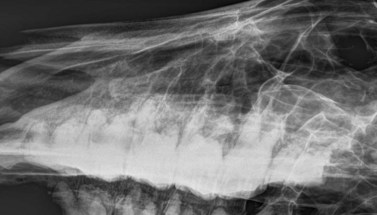

Lateral projection (Figs 13.513.7)

The lateral view is useful to visualize fluid lines and abnormalities of the maxillary or frontal bones or within the paranasal sinuses because the anatomy of the sinuses is not distorted by obliquity of the X-ray beam. The major disadvantage of the lateral view is that lesions cannot be localized to the left or right sides because both sides are superimposed. For this same reason, individual cheek teeth apices cannot be evaluated using this view.

Lateral views of the mandibular cheek teeth are less frequently indicated, but the beam should be centered over the area of interest (usually indicated by a discharging tract or mandibular swelling), and rostrocaudal collimation should be adjusted to include the entire cheek teeth row, if possible. The thick masseter and pterygoideus muscles overlie the caudal three mandibular cheek teeth (Fig. 13.7), and hence higher exposures are required to image the apices of these teeth as compared to the rostral mandibular cheek teeth.

Fig. 13.7 Lateral radiograph of a normal mandibular cheek tooth row. Note that the soft tissue opacity of the thick masseter and pterygoideus muscles are superimposed over the caudal 3 cheek teeth.